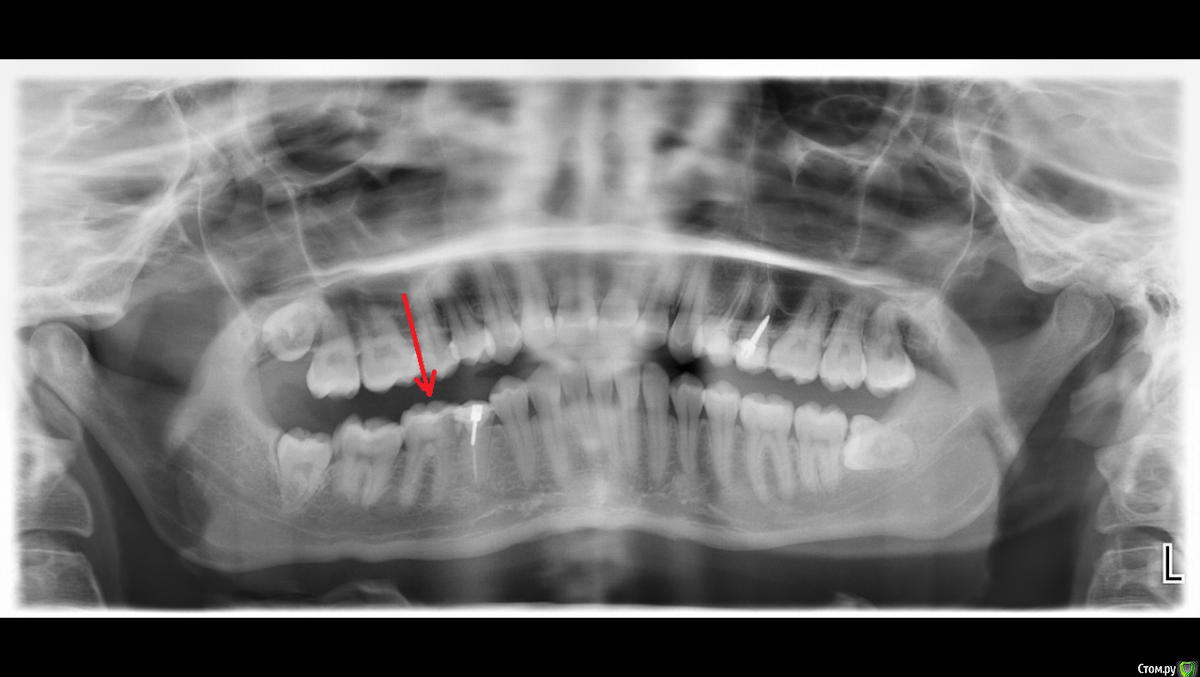

St. Опубликовано 14 марта, 2016 Поделиться Опубликовано 14 марта, 2016 В прошлый раз кололи артикаин, не подействовал. Завтра попробуют ультракаин, если не поможет, не знаю даже как лечить((( У них одно действующее вещество. Но думаю сложность не в этом. Скорее всего у вас не совсем типичное расположение нерва и у доктора не получается довести лекарство куда нужно. На следующий раз перед приемом выпейте пакетик нимесила, это может помочь. Если нет есть два пути- первый менять "мышьяк" пока нерв не "умрет" или второй попросить чтобы уколол кто-то другой из клиники(в идеале хирург) или увы сменить клинику. 1 Ссылка на комментарий